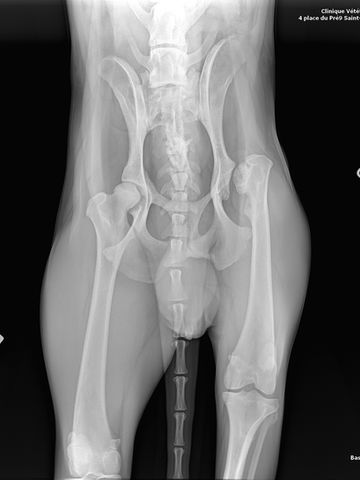

Florence ließ es untersuchen und röntgen und bekam folgende Diagnose:

Alte Läsion des linken Hinterteils mit dorsaler Dislokation und starker Verkürzung des linken Hüftkopfes

Abnormalität bei der Palpation der knöchernen Reliefs, schiefes Becken, Längendyssymmetrie mit Verkürzung der linken Hinter- bis Hyperextension, der Hund Zeigt keine Schmerzen. Verdacht auf Dislokation der linken Hüfte.

Röntgenaufnahmen unter Narkose (Beckengesicht und Profil): alte Läsion, die sich für mindestens 6 Monate zurück liegt (kortikal gut ausgeprägt), große dorsale Verschiebung des linken Femurkopfes mit starker Verkürzung des Hüftkopfes. Es besteht die Gefahr einer Läsion der Ischias bei einem chirurgischen Eingriff, angesichts der dorsalen Verschiebung.